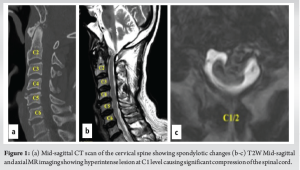

A 74-year-old male patient, a known case of diabetes mellitus, hypertension, and with a history of rheumatic heart disease presented to our outpatient clinic with complaints of upper cervical pain for 1½ months, associated with unsteadiness while walking. He used to work as a bus driver but had to stop due to loss of hand dexterity, weakness, and pain. Neurological examination revealed weakness in all four limbs (motor power- 4/5 according to MRC grading). Both biceps and knee reflexes were exaggerated (3+), plantar response was extensor and he was unable to perform tandem walking. Cervical radiographs showed spondylotic changes without signs of any obvious instability and magnetic resonance imaging revealed a hyperintense lesion at the C1 level in the T2W mid-sagittal image causing significant compression and thinning of the spinal cord (Fig. 1). CT angiogram was performed and revealed a normal course of the bilateral vertebral arteries. After careful evaluation, surgical decompression of the spinal cord using a transoral approach and posterior stabilization of the upper cervical region was planned for the patient.